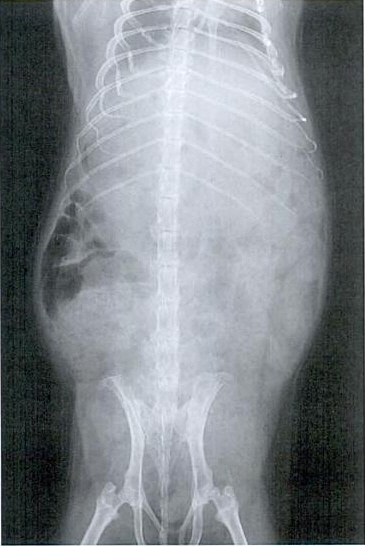

Ukoliko se plinovi ne riješe unutar par dana, potrebno je pronaći točan uzrok, pri čemu može pomoći RTG snimak.

Snimka normalnog abdomena:

Snimka plinovima ispunjenog abdomena: